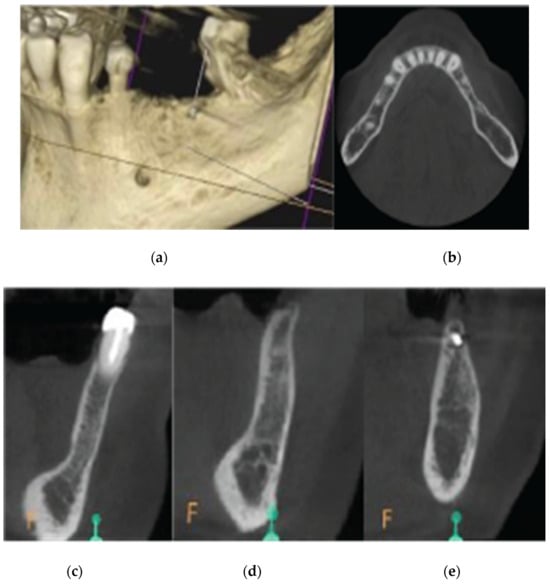

| CASE1-14 | 1 mm | 0 | 1.80 |

| 3 mm | 3.60 | 9.45 | |

| 5 mm | 5.40 | 11.10 | |